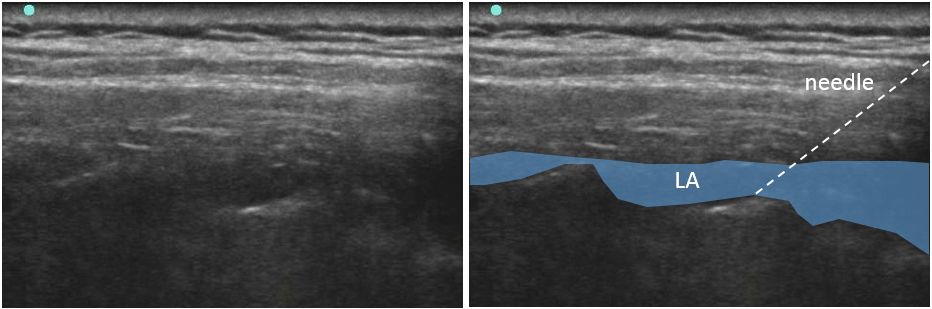

平行法で針をすすめ、0.375%ロピバカイン30mLを注入したのが次の図です。

針の向こうは骨ですから、気胸などの合併症を気にすることはありません。

背部正中線から1.5cmですから、ブラインドでも比較的安全に施行できます。